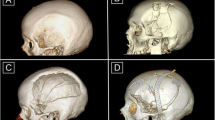

A computer-aided design of a patient-specific porous polyethylene implant was created based on detailed 2 mm bone CT scans. Most designs were based on the shape and curvature of the contralateral side when available. In bifrontal cases, the design engineer collaborated with the neurosurgeon to determine a shape that would work with the patient's anatomy and meet the neurosurgeon's requirements. Bifrontal cases were usually designed in two pieces to facilitate placement (Fig. 1).

The operation was standardized. The entire head of the patient was preoperatively shaved and bandaged with a disinfectant (peroxyacetic acid) for 12 h. Standard intraoperative antibiotic prophylaxis was administered (Cefazolin). During operations, the patient's head was fixed in a Mayfield fixator. After the scalp incision, the skin flap was separated from the dura mater, duraplasty and bony margins. To prevent epidural hematoma, tack-up sutures were routinely used around the edge of the craniotomy. A custom-made PE implant without flange was then inserted into the bone defect. The implant was fixed with miniplates. In cases of bone flap resorption, the partially resorpted bone flap was removed before insertion of the PE implant. The temporalis muscle was separated from the duraplasty and placed above the implant in an orthotopic position (Fig. 2). A vacuum drain was inserted subgaleally for 24 h. Due to the implant's porous structure providing adequate drainage of the epidural space, additional burholes were not performed in the implant. The galea and skin were sutured.

During the monitored period, 30 cranioplasties were performed in 30 patients. The cohort of patients included 23 men and seven women with an average age of 37 years (range 18–70). All patients were preoperatively in good clinical condition with a Glasgow Coma Scale (GCS) of 15. The primary diagnoses were: 14 traumatic brain injuries (TBI), six tumors (two meningiomas, two gliomas, two calvarial tumors), five intracerebral hemorrhages, three brain abscesses, one cerebral venous sinus thrombosis and one inflammatory demyelinating disease. Cranioplasty was performed 23 times (76,7%) due to a bone defect after hemispheric decompressive craniectomy, five times (16,7%) after limited size craniotomy and twice (6,7%) after bifrontal decompressive craniectomy. Demographic and preoperative data are summarized in Table 1.

The area of the implant was, in 25 cases (83,3%) larger than 100 cm2, and five times (16,7%) the implant was smaller than 100 cm2. Secondary cranioplasty (failure of the previous primary cranioplasty) was performed in 19 patients (63,3%) and primary cranioplasty in 11 patients (36,7%). The timing of cranioplasty was more than three months after the previous surgery in 27 patients (90%) (late cranioplasty) and less than three months after the previous surgery in three patients (10%) (early cranioplasty). The average operative time was 120 min (range 60–210), and the average intraoperative blood loss 241 ml (range 60–885). The average hospital stay was nine days (range 4–14). The price of the implant ranged from 3996 to 9069 Euros (on average 4499 Euros) depending on the size.